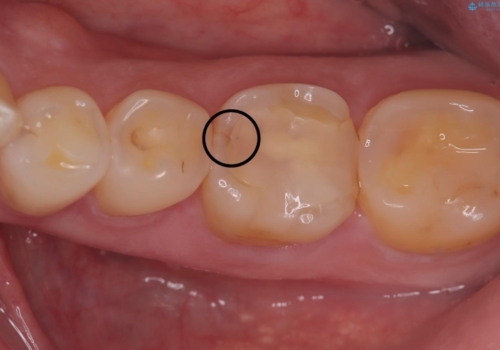

よく見ると歯冠部に咬合面から近心側にのびるヒビ(クラックライン)が入っているのが見えます。

各種検査を行い、咬合面にヒビ(クラック)を認めました。